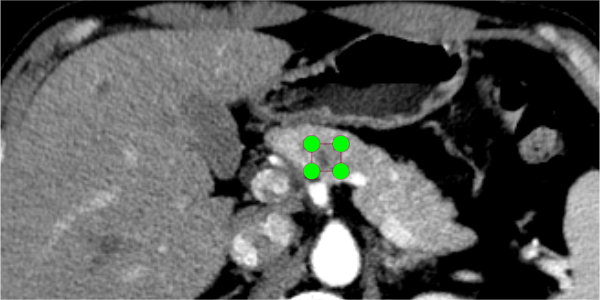

Firstly, there is often a correlation between the type of lesion and its location. Such as mucinous cystic neoplasms (MCNs), a type of pancreatic cystic neoplasms (PCNs), most commonly occurs in the pancreatic body and tail [5]. Existing methods [6] mainly focus on the area of the lesion and do not fully utilize the information surrounding the lesion. Secondly, the traditional detectors [8, 10, 16] has two drawbacks when performing multi-scale feature fusion: (1) direct fuse of different layers of features reduces the representation of multi-scale features, (2) top-down transfer of features leads to loss of information. When the lesion area occupies only a small fraction of the pixels in CT scan image, or when the difference in features between the lesion area and the non-lesion area is not obvious, the loss of detail information makes it difficult to identify and localize the lesion. Fig. 1 illustrate visualization of CT scan with distinctive and less distinctive lesion features.

Across-layer. When inconspicuous lesion boundaries and small lesions appear (such as in Fig. 1 (b)), the amount of detail information determines the success of screening and detection. However, the traditional top-down and bottom-up transmission modes may lead to information loss, as each layer only receives complementary neighboring information while the cross-layer information (e.g. to ) is weakened and lost during transmission. Inspired by Glod-YOLO [28], we propose the AFW block, which first extract global effective features directly through across-layer feature gather (AFG) block to reduce the information loss. To retain more information about the positions of small targets, we specifically introduce the low-level feature map into the AFG block. After extracting the global features, they are assigned to different hierarchical levels. It’s worth noting that directly fusing information of different densities may lead to semantic conflicts, thus limiting the expression of multi-scale features. Here, we design the split feature weighting (Split FW) block with different weights for each levels to fuse global features and filter conflicting information.